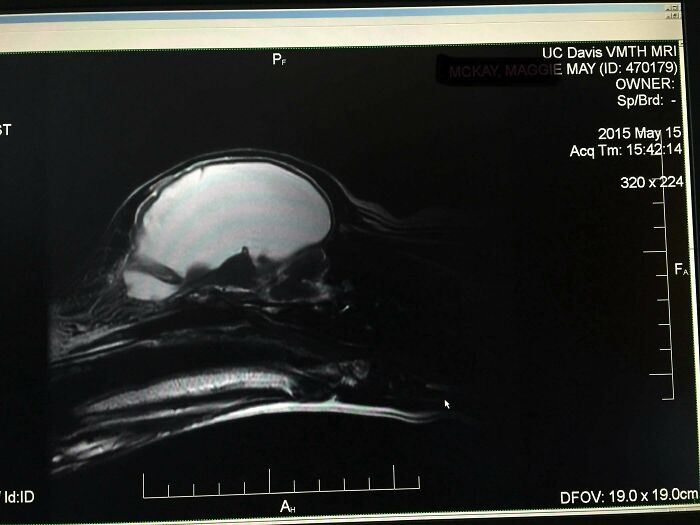

Собака прожила жизнь почти без мозга

Собака родила щенков, вела обычную жизнь, но всегда была немного странной. После припадка МРТ показал: её мозг сжат до тонкой корки, остальное — вода. Низкий натрий помогал поддерживать баланс. Ветеринары были в шоке, что животное вообще ходит. Отправили домой с обильным питьём — собака благополучно дожила до 12 лет.